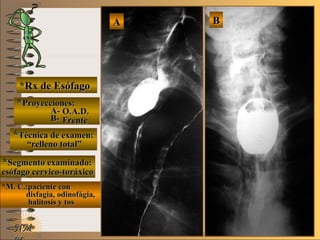

NMNM

*Rx de Esófago*Rx de Esófago

**Proyecciones:Proyecciones:

A-A-

B-B-

**Técnica de examen:Técnica de examen:

**Segmento examinado:Segmento examinado:

*M. C.:paciente con*M. C.:paciente con

disfagia, odinofágia,disfagia, odinofágia,

halitosis y toshalitosis y tos

BBAA

O.A.D.O.A.D.

FrenteFrente

““relleno total”relleno total”

esófago cervico-toráxicoesófago cervico-toráxico

A-A-El examen es normal o patológico?El examen es normal o patológico?

Examen patológico de esófago toráxico superiorExamen patológico de esófago toráxico superior

con técnica de relleno total en proyecciones:con técnica de relleno total en proyecciones:

A- O.A.D. y B- frenteA- O.A.D. y B- frente

B-B-La patología es congénita o adquirida?La patología es congénita o adquirida?

Patología adquiridaPatología adquirida

C-C-Dicha patología es orgánica, funcional o mixta?Dicha patología es orgánica, funcional o mixta?

**OpciónOpción

D-D-La misma es neoplásica o no neoplásica?La misma es neoplásica o no neoplásica?

Patología adquirida orgánica no neoplásicaPatología adquirida orgánica no neoplásica

E-E-Puede describir la o las imágenes patológicas?Puede describir la o las imágenes patológicas?

Se identifica unaSe identifica una imagen de adición o deprimidaimagen de adición o deprimida

UNTUNT (ver(ver TerminologíaTerminología UNTUNT )) divertículo de Zen-divertículo de Zen-

ker en esófago cervical, sobre el borde posterior,ker en esófago cervical, sobre el borde posterior,

y se distingue también “pintado” con bario a lay se distingue también “pintado” con bario a la

pared anterior de la tráqueapared anterior de la tráquea

**Opción avanzada para volver a ver las imágenes con reparosOpción avanzada para volver a ver las imágenes con reparosNMNM

Patología adquirida orgánicaPatología adquirida orgánica

A- O.A.D.A- O.A.D.

B- FrenteB- Frente

divertículodivertículo

volvervolver

paredpared

anterior deanterior de

la tráqueala tráquea

con bariocon bario

(tos)(tos)

nivel hidroaéreonivel hidroaéreo

(paciente de pie)(paciente de pie)compresióncompresión

divertículardivertícular

(disfagia)(disfagia)